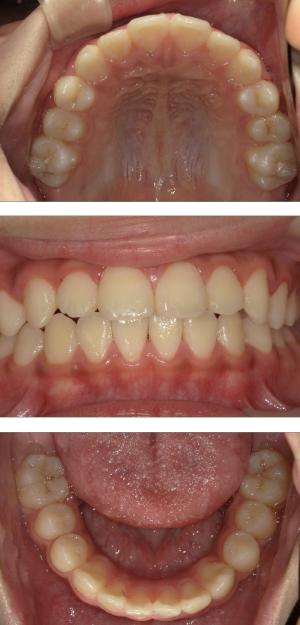

- 歯並びの改善

- 歯を動かすのではなく顎の成長を促す

- 非抜歯矯正ができる

- 側方拡大だけでなく前方成長も促す

- お顔の成長が正しく美しく導くことができる